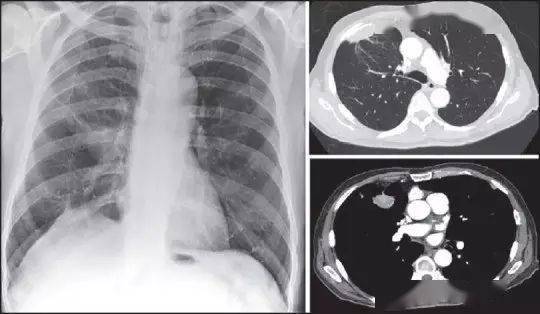

除了肿瘤类型,还有一些其他因素也可能与癫痫有关。大约30%的脑肿瘤患者在手术后因脑组织损伤或瘢痕形成而出现继发性癫痫。老年人群中,颅内肿瘤如转移瘤也是癫痫的常见病因之一,常常与脑血管病变同时存在。